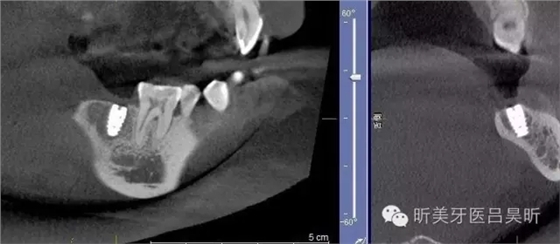

本次病例介紹一例簡單種植,根據(jù)患者術(shù)前CBCT,因牙槽骨的形態(tài)特殊性,會為種植帶來一定的難度,對于經(jīng)驗豐富的醫(yī)生可能會掌控自如,但在操作上的風(fēng)險會增加,通過導(dǎo)板技術(shù)可減少風(fēng)險發(fā)生并能實現(xiàn)精準定位。

術(shù)前CBCT截圖,垂直骨量似乎感覺良好

可見種植位點舌側(cè)區(qū)凹陷,牙槽骨上部舌傾明顯。

術(shù)后CBCT 檢查,植入位點良好,與術(shù)前設(shè)計基本一致,并實現(xiàn)安全植入。